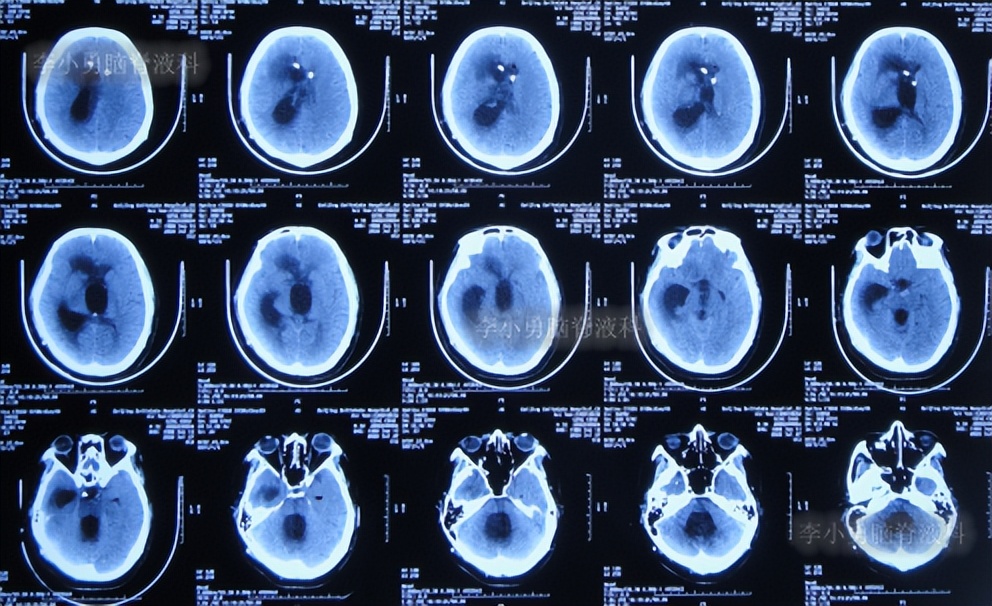

鞍上池脑囊虫性脑积水,三脑室造瘘术无效,2次分流术却均堵管分流重感染致脑室重度粘连,李小勇脑脊液科经3次艰难治疗后获“满意”结果

二、第1次在李小勇脑脊液科治疗过程和结果

2020年6月4日(脑囊虫切除术+第三脑室造瘘术后2年5个月,2次脑室腹腔分流术均堵管,期间历经5次住院但脑积水仍反复复发)住入李小勇脑脊液科,入院时:神志朦胧,饮食差,问答有误,自己站立不稳,双眼对视(图-19);既往史:口服抗癫痫药物,青霉素过敏。头颅CT示鞍上占位术后,脑室内可见引流管,脑室系统扩张(图-20)。

图-20:2020年6月4日头颅CT